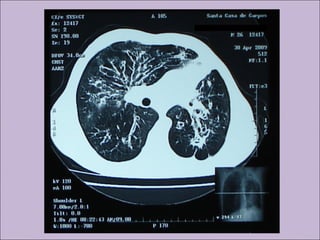

C) Anormalidades persistentes à radiografia de tórax

Bronquiectasias

Manifestações sino-pulmonaresManifestações sino-pulmonares A)Colonização / infecção persistentes por patógenos típicos da FC como Staphylococcus aureus, Haemophilus influenzae, Pseudomonas aeruginosa e Burkholderia cepacia B) Tosse crônica e produtiva C) Anormalidades persistentes à radiografia de tórax D) Obstrução das vias aéreas E) Pólipos nasais, sinusite F) Baqueteamento digital Rosenstein. J Pediatr. 1998;132:389-95

COMPLICAÇÕES DA FIBROSECÍSTICA RESPIRATÓRIAS Bronquiectasias Atelectasias Hemoptise Pneumotórax Pólipos nasais Sinusite Hiperreatividade Cor Pulmonale Ins. Respiratória Impactação mucóide ABPA GASTROINTESTINAIS Íleo meconial Peritonite meconial SOID Prolapso retal Intussucepção Volvo intestinal Colonopatia fibrosante Apendicite Atresia intestinal Pancreatite(s) Cirrose biliar Icterícia neonatal colestática Esteatose hepática DRGE Colelitíase Failure to thrive Def vits ADEK In Pancreática Diabetes OUTRAS Infetilidade Atraso puberal Edema-hipoproteinemia Desidratação grave/choque Osteoartropatia hipertrófica Baqueteamento digital Amiloidose Diabetes mellitus Kliegman: Nelson Textbook of Pediatrics, 18th ed., 2007